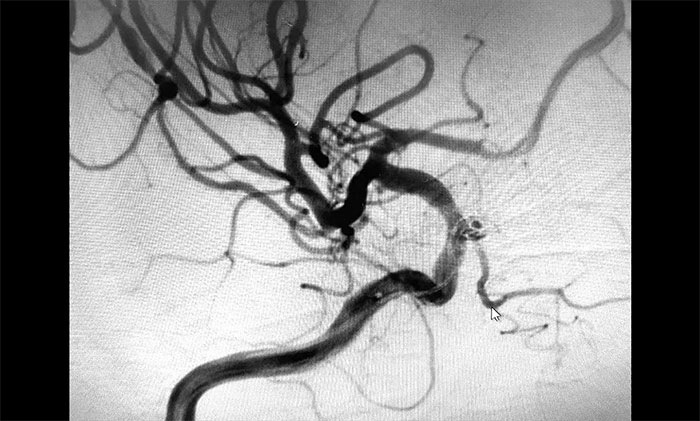

▲动脉瘤栓塞

▲栓塞后,载瘤动脉血流通畅

术中,在微导丝的引导下将微导管头端小心送入动脉瘤腔内,之后顺着这个通路往动脉瘤内填塞弹簧圈,造影显示动脉瘤瘤内造影剂明显滞留,眼动脉(载瘤动脉)血流通畅。遂解脱弹簧圈并释放支架,再次造影,支架覆盖动脉瘤,贴壁良好。整台手术历时90分钟顺利完成,患者术后恢复情况良好。